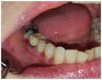

Figure 11

Figure 11. Hyperplastic candidosis associated within the edentulous ridge 47-48-retromolar region in a diabetic with poor denture hygiene